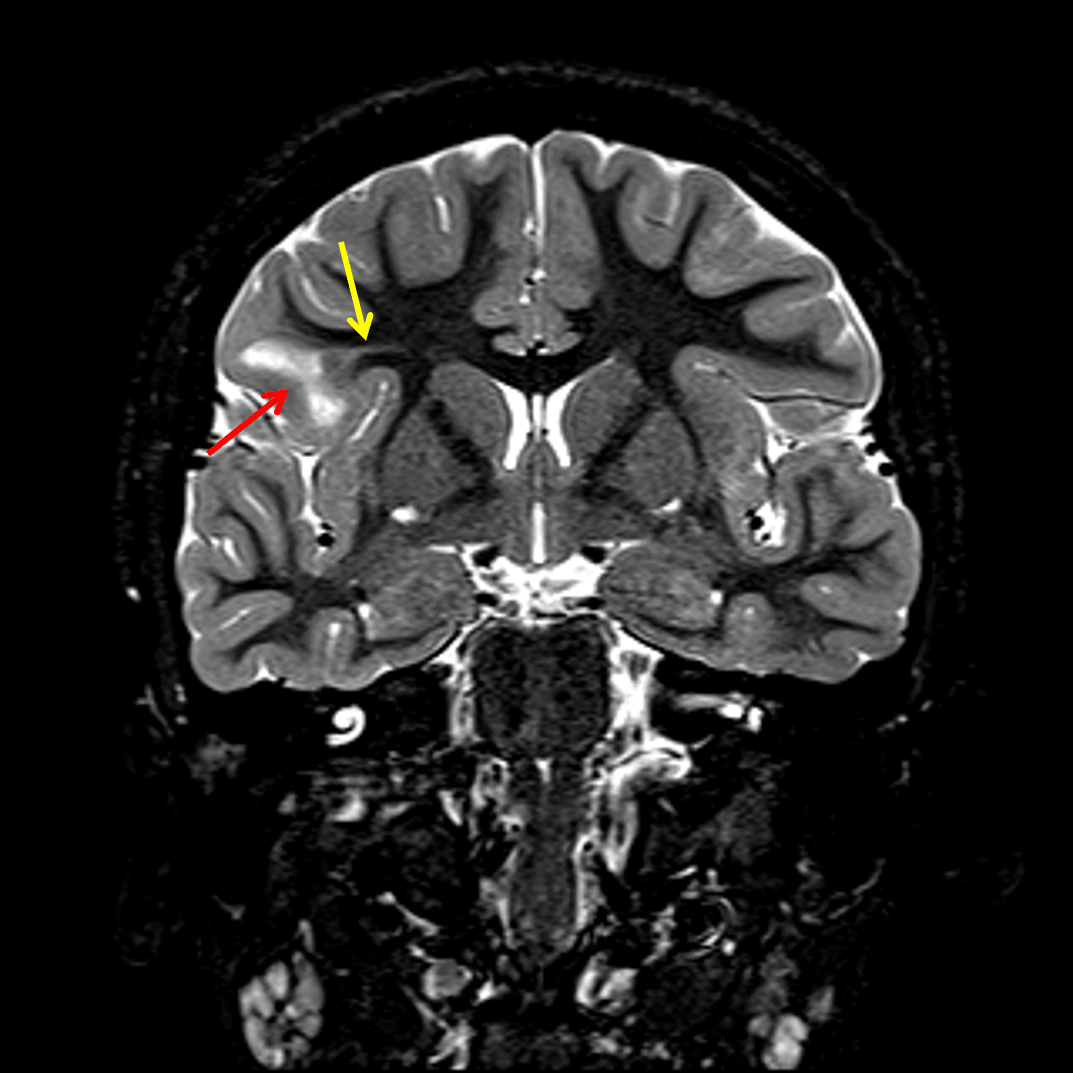

- Area of nonmasslike T2/FLAIR signal hyperintensity involving the cortex and juxtacortical white matter of the right inferior frontal gyrus and more subtle T2/FLAIR hyperintense signal radiating deep toward the ventricular margin

- Associated blurring of the gray-white interface

Abnormal cortical and juxtacortical T2 signal hyperintensity involving the right inferior frontal gyrus (red arrow) with an adjacent transmantle sign (yellow arrow).